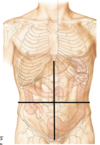

When dividing the abdoment into quatres, what anatomical land mark would you use?

- umbilicus (belly button)

What lies within the upper right quadrant if we divide the abdomen into quatres from the umbilicus?

- right lobe of the liver

- gall bladder

- duodenum (first part of SI)

- head of Pancreas

- hepatic flexure of colon

- small part of ascending and transverse colon

What lies within the upper left quadrant if we divide the abdomen into quatres from the umbilicus?

- stomach

- spleen

- left lobe of liver

- body of pancreas

- splenic flexure of colon

- part of transverse and descending colon

What lies within the lower left quadrant if we divide the abdomen into quatres from the umbilicus?

- small intestine

- descending colon

- sigmoid Colon

What lies within the lower right quadrant if we divide the abdomen into quatres from the umbilicus?

- cecum

- appendix

- ascending colon

- small intestine